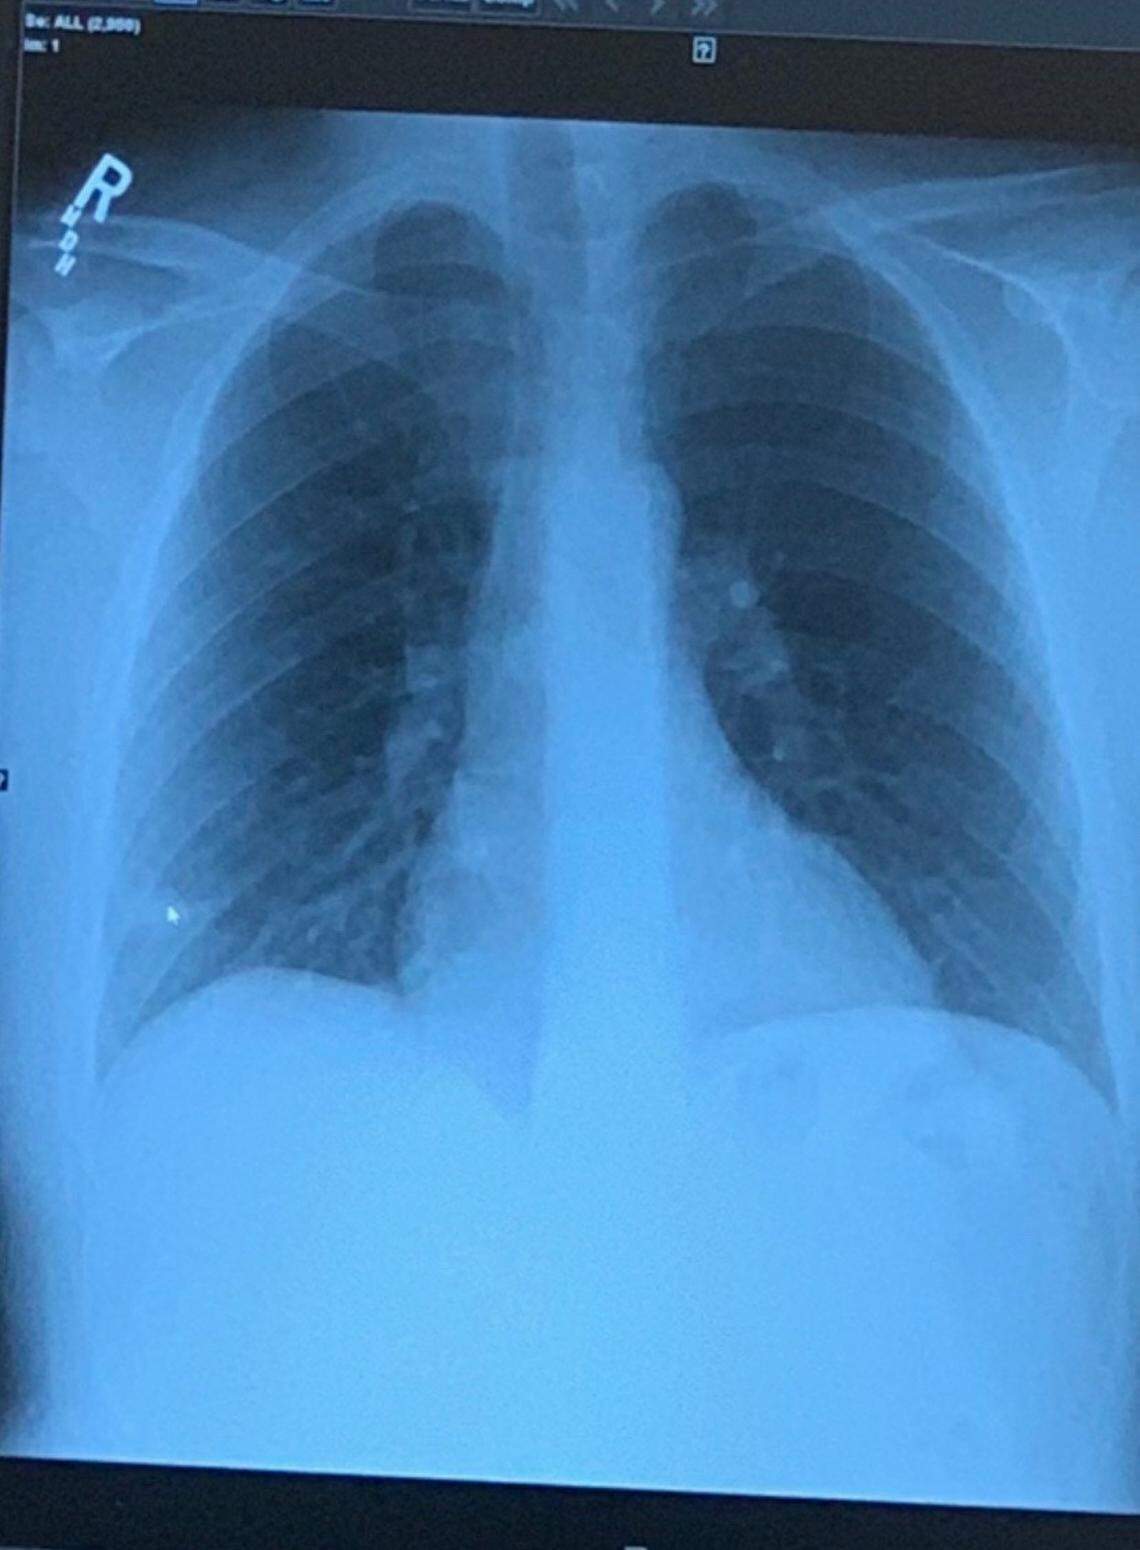

A chest X-ray showed that Josey’s right lung was partially collapsed.

An X-ray image of Jordan Josey’s lungs shows his left lung, on right, partially collapsed. Josey, 28, first felt symptoms of the coronavirus on the morning of March 17. He sought help at a string of medical facilities in Macon.

An X-ray image of Jordan Josey’s lungs shows his left lung, on right, partially collapsed. Josey, 28, first felt symptoms of the coronavirus on the morning of March 17. He sought help at a string of medical facilities in Macon. Contributed photo

At the hospital emergency room, Josey’s blood pressure and heart rate skyrocketed. Even so, his oxygen levels were OK. Barely. He was told that, yes, his lung was in distress and that he needed to do deep-breathing exercises to re-inflate it.